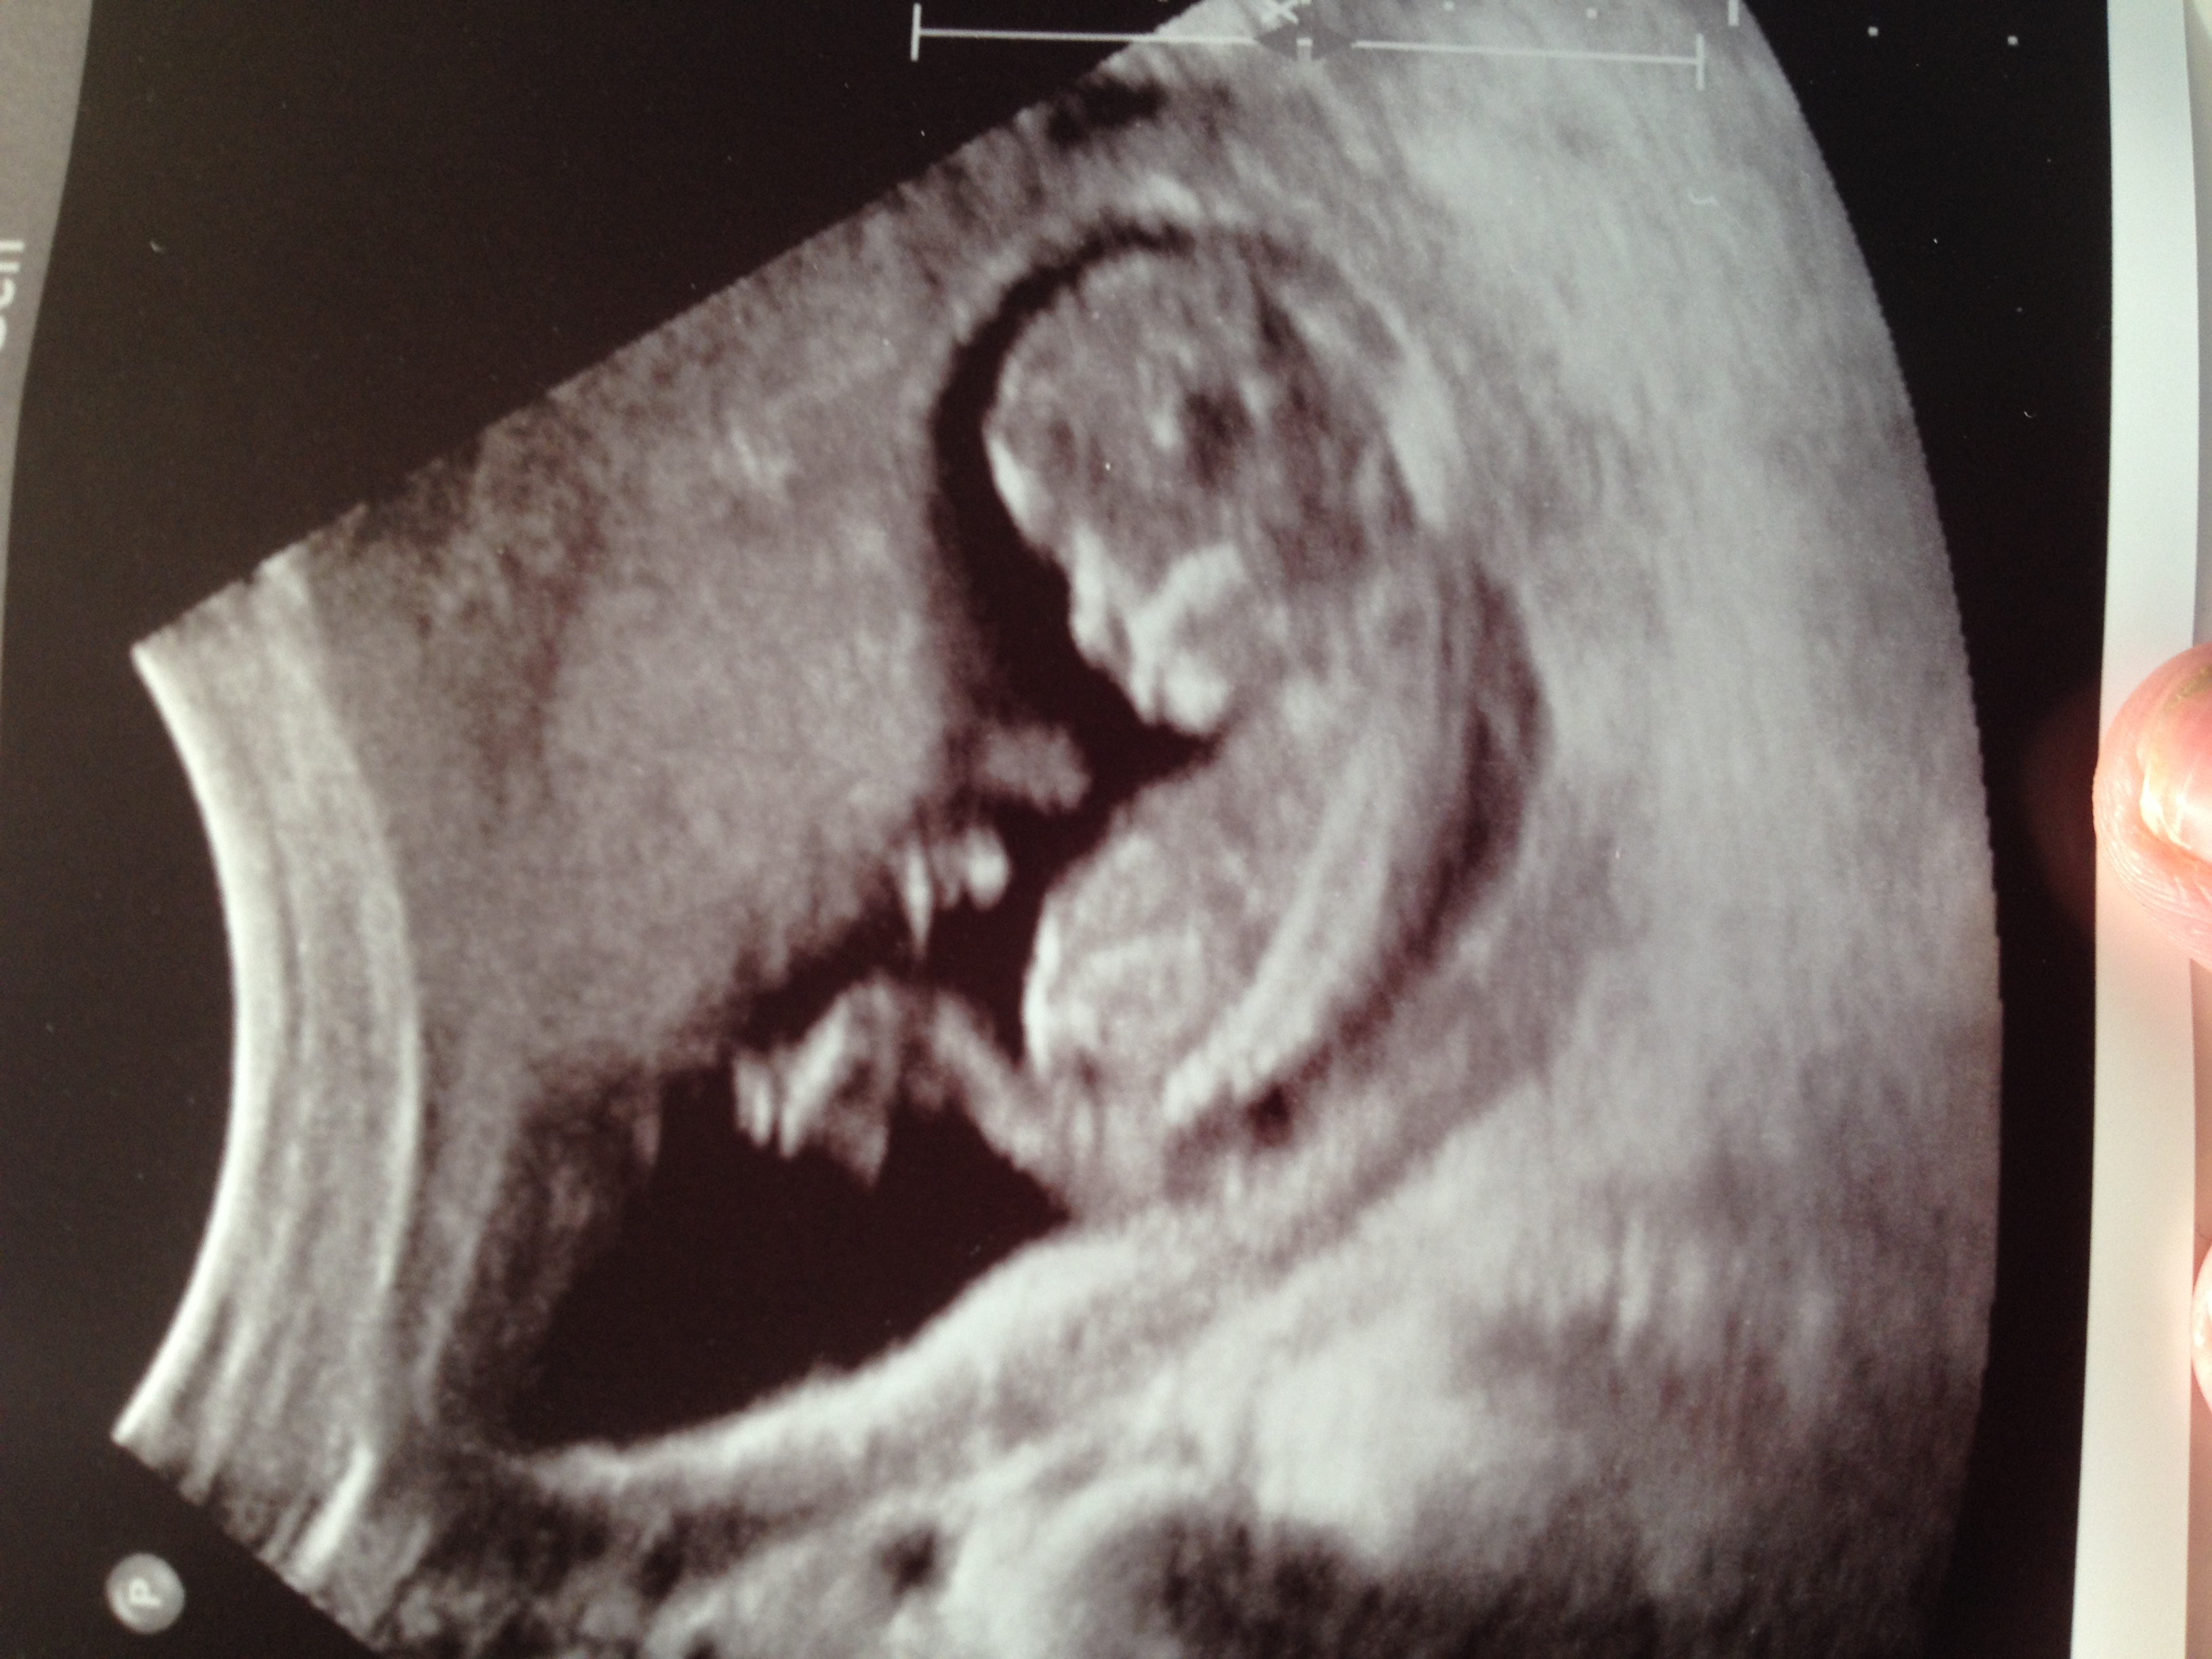

Any guesses? 12w6d Attachment 17116

By the roundness of the skull I wouldsay girl just a a guess